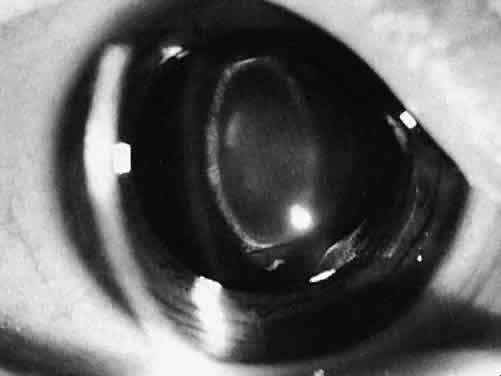

Failure of a pupil to dilate fully is common because of the presence of synechiae (Fig. 9) or relatively atonic pupillary dilator muscles (rubella and Marfan's). If the pupil is small or synechiae are noted, the location of the incision can be adjusted or a paracentesis tract or tracts can be placed to allow iris manipulation with instruments or the insertion of iris retracting hooks. If the pupil is 2 mm or smaller, a sphincterotomy may be necessary. This procedure can be accomplished by cutting the iris sphincter with a suction cutting instrument or a Vannas scissors.

Fig. 9. A cataract that resulted from repeated episodes of uveitis. The pupil will not dilate because of lens-iris synechiae.